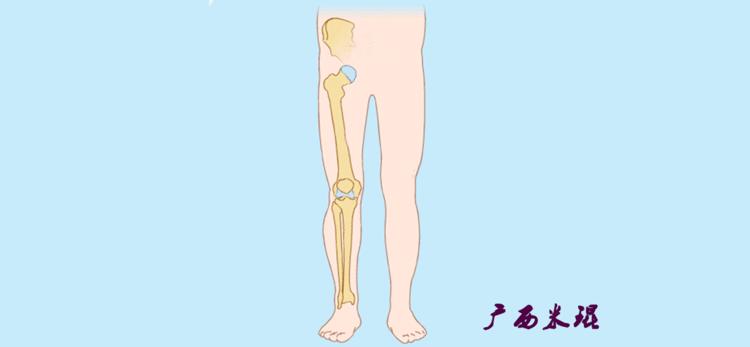

我们说了这么多照片的下肢力线测量,体表也是可以粗略测量的,自股骨头中心至踝关节中心拉一直线,髌骨中心点位于此直线上;自髂前上棘至踝关节中心拉一直线,髌骨中心点位于此直线内侧;自髂前上棘至第1、2趾间拉一直线,髌骨中心点位于或接近此直线。

(3)垂直轴

也就是下肢的负重轴,它是身体的纵轴线,与地面垂直,由于双髋比双踝的距离宽,所以垂直轴与下肢力线(机械轴)存在3°的外翻。

最常见的下肢畸形发生于冠状面,即膝内外翻畸形,冠状面的对线异常通过应用“对线异常检验”进行分析,机械轴的偏移(MAD)表现为对线异常。

膝内翻是指下肢力线通过膝关节中心点内侧,距中点2mm以上,偏内超过15mm为显著膝内翻。膝外翻是指下肢力线通过膝关节中心点外侧,距中点2mm以上,偏外超过10mm为显著膝外翻。